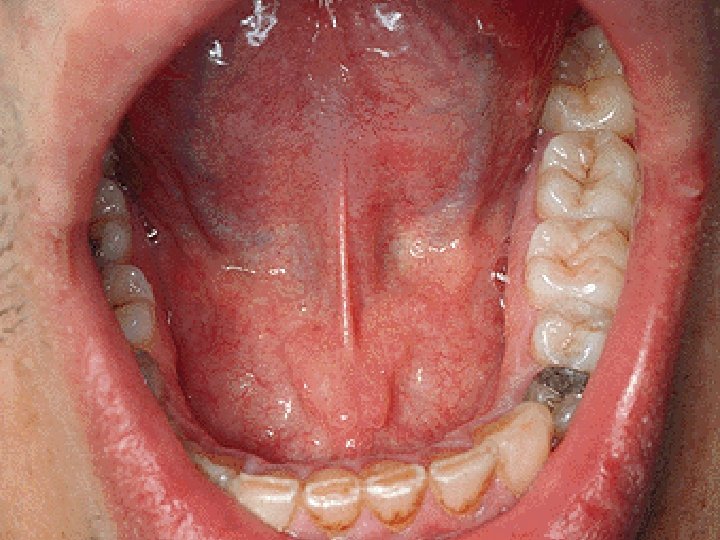

Facies inferior linguae Plica fimbriata Frenulum linguae Plica sublingualis